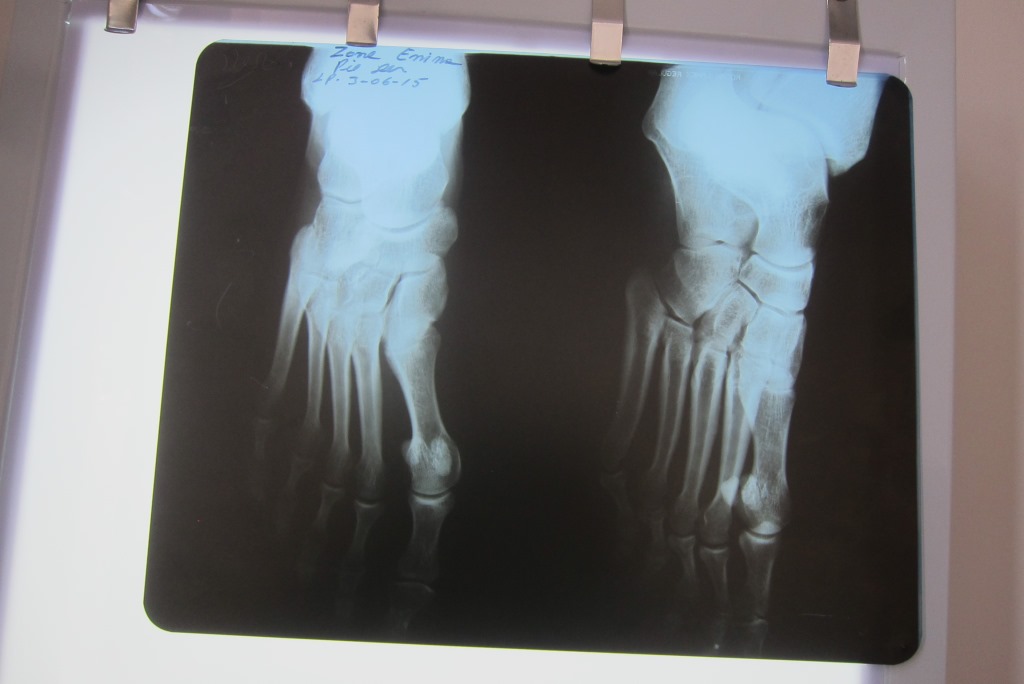

Tieku iesaukta nelielā skabūzī, kas piebāzts ar smalka izskata aparātiem, vienīgais, kas izskatās drusku nokalpojis, ir rokas rentgens. Bet bilde uztaisīta tiek un drīz jau dakteris ir gatavs apskatīt to komplektā ar mani. Ārsts ir laipns un pļāpīgs un, kad izspēlēju „veco joku ar žurnālisti”, tad vispār viņš top sirsnības kalngals. Atvainodamies, ka nesot nekāds Da Vinči, šis zīmē manu kāju un stāsta, kur ir problēma. Ar kauliem ir viss ir kārtībā, esot traumētas saites. Jā, lai tik turpinot lietot aptiekā ieteikto smāķi, 5 dienas padzerot šaibas, pa dienu pārvietojoties ar elastīgo saiti, bet labāk vispār kādu nedēļu vai divas īpaši nepārvietoties ar kājām. Uz atvadām dakteris piekodina, lai noteikti atsūtu e-pastu, kā būs veicies ārstniecības process un grib par katru cenu nobildēties kopā ar mani un komandu. Manas sākotnējās bažas par izmaksām ir pāraugušas vieglā jautrībā par notiekošo un priekā par faktu, ka nekas nav lauzts un, galu galā, ja tā labi padomā – kas ir 75 dolāri (vēl 72 boliviano atstāju aptiekā) par veselību un sirdsmieru!